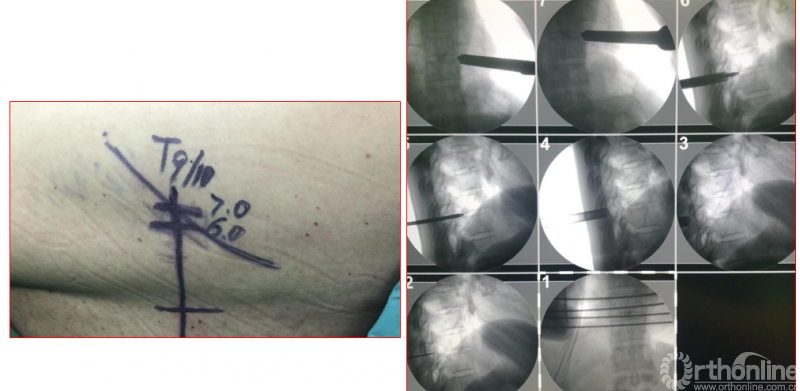

术中资料

点击以上图片,查看术中视频(超链接:http://res.orthonline.com.cn/video/case5---20.mp4)

点击以上图片,查看术中视频(超链接:http://res.orthonline.com.cn/video/case5---30.mp4)